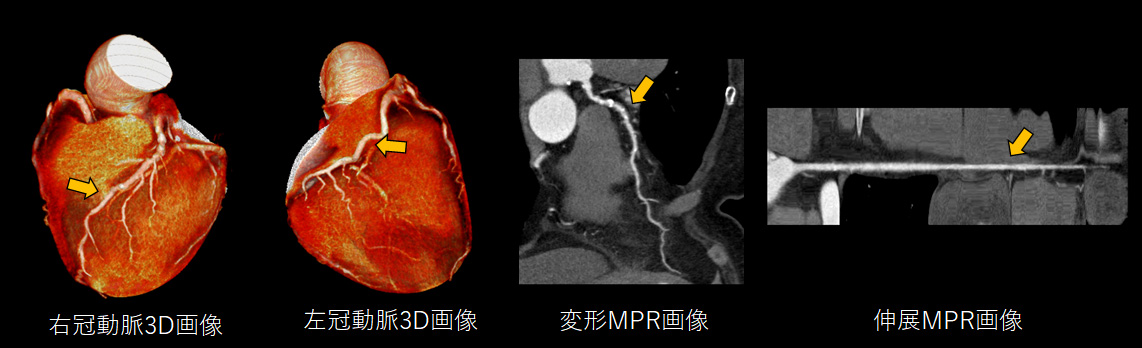

循環器領域 では高速撮影の利点を活かした静止画像を作成

心臓は握りこぶし程の小さな臓器であり、その血管はさらに微細かつとどまることなく常に動き続けています。この血管を静止画像として画像化することは非常に困難なことですが、最速0.35秒で撮影が可能な当院の撮影技術を最大限に活かすことで、心臓においても他の動きのある臓器同様に動きやボケのない画像提供が可能です。心臓の血管の石灰化などを評価することで、治療に役立てます。

3D画像 を用いた手術シミュレーションにより安全な手術を提供

CT検査で撮影した画像を最大限有効活用して、診断用・治療用・患者様説明用に3D画像を作成しています。3D画像は、CT画像と比べて多彩かつ立体感があるため、誰が見ても病態を理解しやすい特徴があります。また医療従事者にとっても手術のシミュレーションをする際に欠くことのできない存在です。

これらの精細な画像を機械的に作成することは困難であり、非常に多くの知識と高度な技術が必要となります。当院では人の手による高精細かつ丁寧な画像提供を行っています。